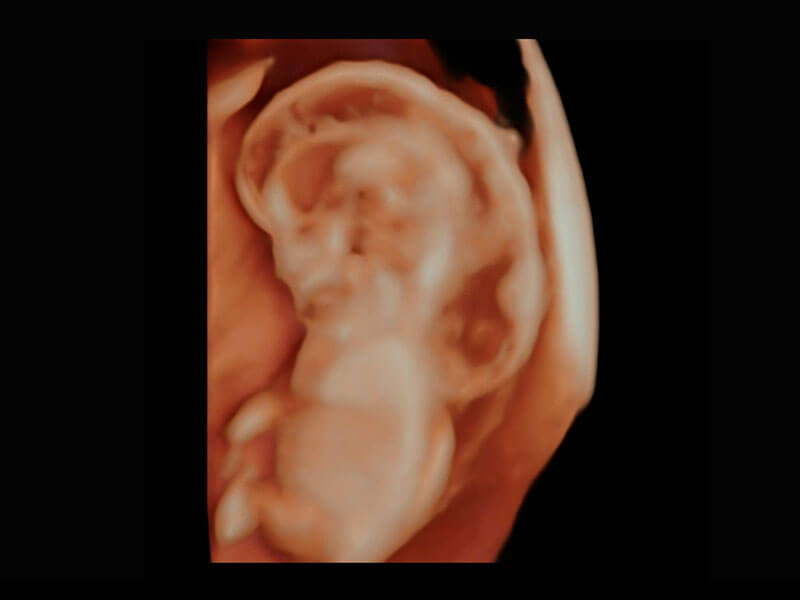

P60在胎兒早孕期超聲篩查中為您帶來優(yōu)異的圖像質(zhì)量。

高分辨率容積成像-早孕胎兒